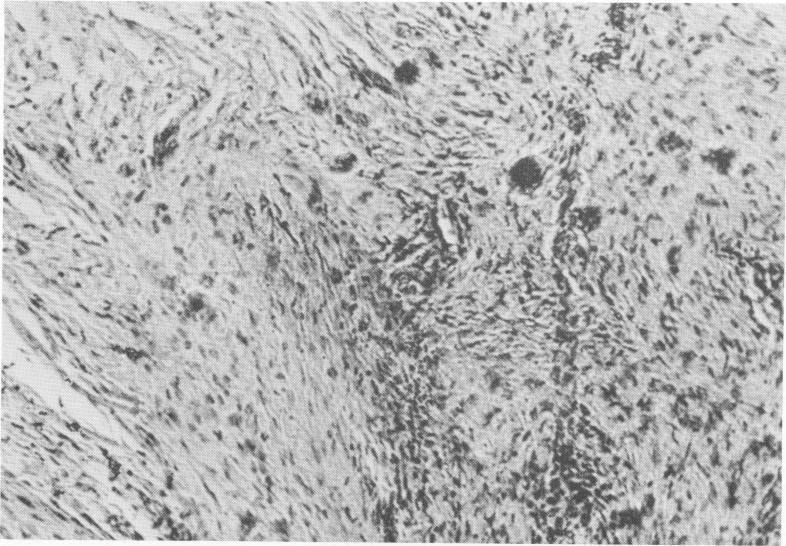

Fig. 4-11. Fibrous tissues with fibrocytes and some plasmodial elements. (From Chercheve, R.: Les implants endo-osseux, Paris, 1962, Librairie Maloine.)

2 Fibrocytes and plasmodial elements at Formiggini implant site